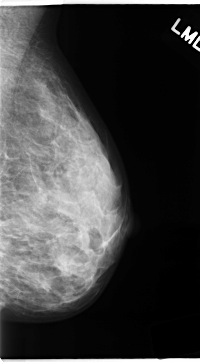

C_0139_1.RIGHT_MLO

RIGHT_CC LINES 4696 PIXELS_PER_LINE 2664 BITS_PER_PIXEL 12 RESOLUTION 50 NON_OVERLAY